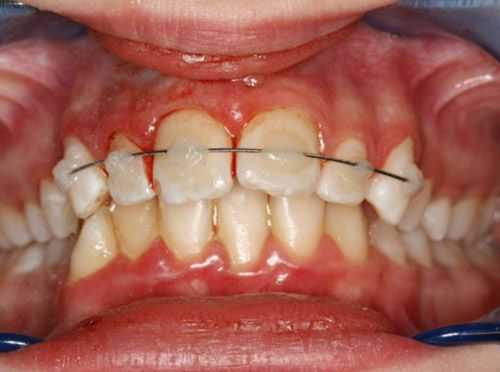

- хроническая — длительное давление на зуб из-за неправильного расположения зуба в зубном ряду или некорректного лечения: неправильной установки внутриканального штифта при эндодонтическом лечении (лечении корневых каналов) или брекет-системы при ортодонтическом лечении [17] .

После проведённых лечебных мероприятий вывихнутый зуб иммобилизируют (обездвиживают). Для этого врач использует индивидуальную шину-каппу, изготовленную непосредственно на пациенте. В шину обязательно включают не менее двух здоровых зубов по обе стороны от неполного вывиха. Шину накладывают минимум на 5-6 недель.